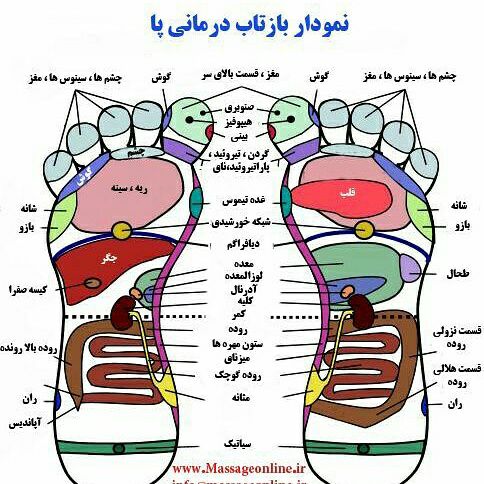

همراه با ماساژ